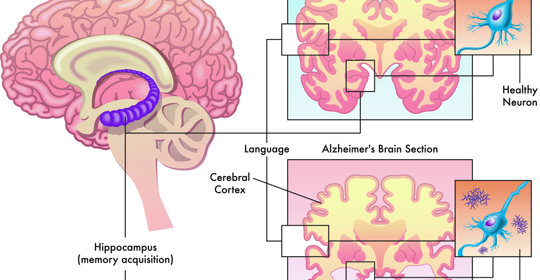

腦炎後遺症:病因與治療

腦炎後遺症:主要致病原因及後期症狀

腦炎後遺症:急性腦炎、病毒性腦炎